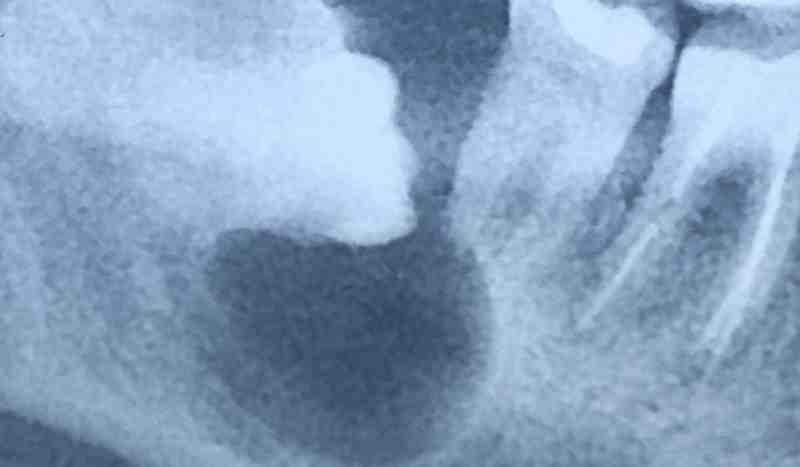

Поэтому главный вывод: перед удалением нужно не гадать, а смотреть снимок.

Обычный рентген (ОПТГ) уже даёт достаточно информации, чтобы оценить риски.